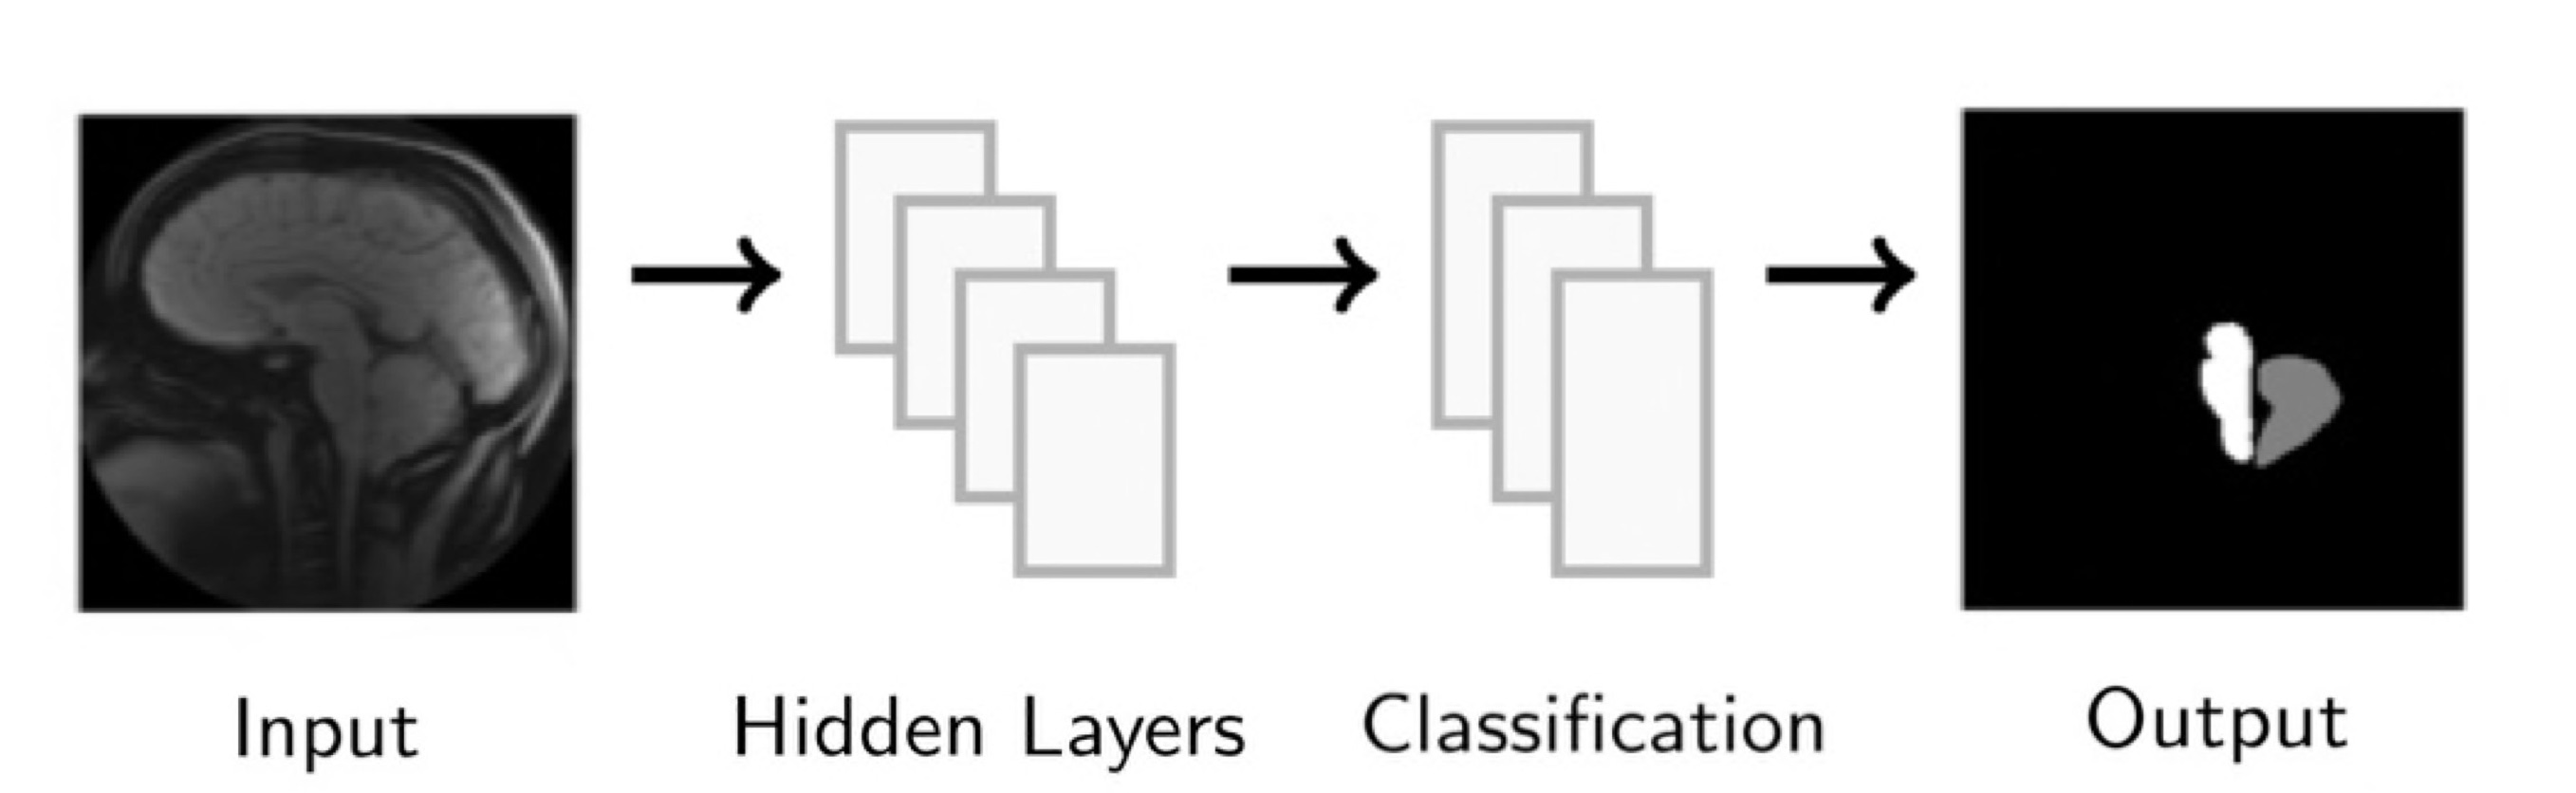

During our summer research at Emory University 2021 REU/RET program, our group focused on the algorithmic diagnosis of Chiari malformation from DENSE MRIs. We created an algorithm that can accurately and efficiently segment the cerebellum and brain stem from a magnitude image and use displacement data to classify whether or not a patient has the Chiari malformation. In doing so, we investigated two approaches; one that segments the given image by aligning and comparing the image to a known atlas and another that segments through deep learning.

We develop this project to solve the problem of identifying where the brain stem and cerebellum are in a given MRI. By finding or, in the language of the field, by segmenting the brain stem and cerebellum, we find the most relevant regions to look at brain movement. Using the DENSE MRI data, we can then average the movement over those regions to produce a biomarker that can help predict whether or not a patient has the Chiari Malformation. By producing these segmentations (examples above) automatically with the machine learning or atlas-based approaches, the diagnosis process could become much cheaper and more efficient.

We develop this project to solve the problem of identifying where the brain stem and cerebellum are in a given MRI. By finding or, in the language of the field, by segmenting the brain stem and cerebellum, we find the most relevant regions to look at brain movement. Using the DENSE MRI data, we can then average the movement over those regions to produce a biomarker that can help predict whether or not a patient has the Chiari Malformation. By producing these segmentations (examples above) automatically with the machine learning or atlas-based approaches, the diagnosis process could become much cheaper and more efficient.

We also looked into a machine learning approach. The goal here was to find a relationship between the DENSE images and their corresponding manual segmentations by training a model using convolutional neural networks (CNN). The network "learns" to identify images features, and, if successful, DENSE images can be used as inputs and the model will automatically segment the brain stem and cerebellum.

Our project implemented a CNN called U-Net, you can find out more about this network and the code we used here: U-Net: A PyTorch Implementation in 60 lines of Code